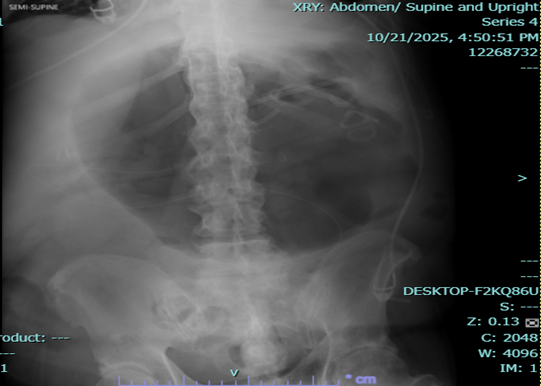

Endoscopic esophagogastroduodenoscopy plus endoscopic internal drainage using plastic stent and insertion of duodenal tube were done on 23 September 2025, repositioned to the jejunum on 29 September 2025. By x-ray (5 October 2025), a gas-filled mass is still appreciated in the upper abdomen, in the region of the stomach. The feeding tube was seen coursing within, with its tip located lateral to the mass, which may be in the distal segment of the stomach. No distinct kink was noted in this study.

The patient was readmitted for fever and anemia, and resolved accordingly. X-ray of abdomen showed unchanged gas-filled focus.

Figure 3a,b: X-ray of abdomen.